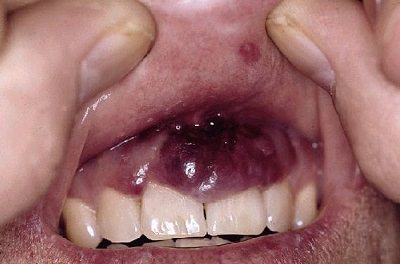

4. Epidemik (AIDS ile Birlikte Olan) Kaposi Sarkomu

AIDS'li hastalarda en sık görülen sarkomdur. Lezyonlar vücutta daha dağınık ve yaygındır, sıklıkla gövde, baş ve boyunda gözlenir. Mukozal ve iç organ tutulumları da görülebilir.

AIDS ile ilişkili KS'ye "human herpesvirus 8 (HHV-8)" neden olur. Kaposi sarkomu, aynı zamanda mukoza tutulumu da gösterebilen bir hastalıktır.